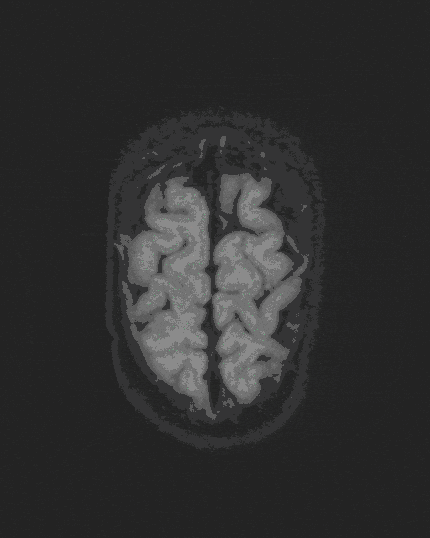

Craniosynostoses

Craniosynostoses are premature ossifications of single or multiple cranial sutures that prevent uniform and harmonious head growth. The result is usually head shape changes without significant clinical relevance.